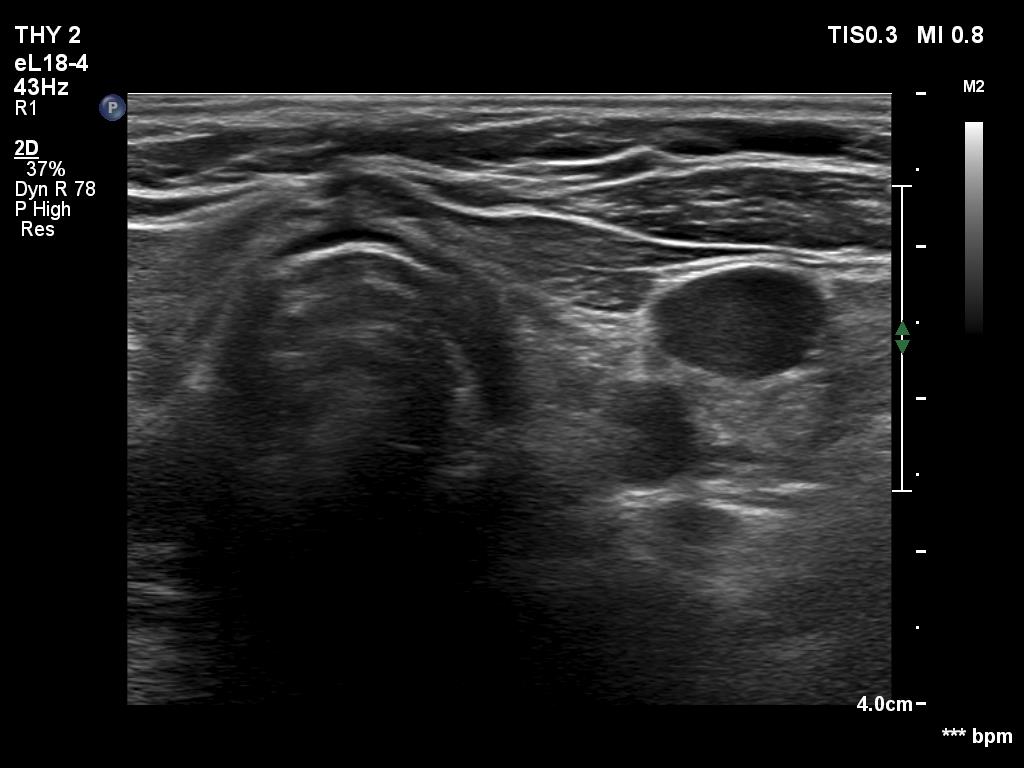

One year after the surgery (second row of images):

Clinical data: On routine follow-up, the surgeon palpated a mass in the middle of the neck. The patient was referred for evaluation and cytology of the mass.

Palpation: a not firm mass in the middle of the neck above the level of the thyroid.

Laboratory tests: TSH 3.01 mIU/L on daily 75 microgram levothyroxine.

Ultrasonography. Connective tissue replaced the thyroid. Approximately 4 cm above the level of the thyroid, a hypoechoic mass was found. The echo structure was identical to the that of the thyroid seen before the surgery.

Cytology was performed form the mass and resulted in benign hormonal atypia. Wash-out thyroglobulin exceeded 10,000 pg/mL.

Comment. The palpation remains a crucial examination in thyroid patients. If we did not palpate the neck, this lesion would be very likely overlooked on ultrasonography because of the similarity of the echo structure to the neighboring muscle tissue. The two types of tissue differed in two things, the thyroid gland contained less thick and shiny connective tissue bundles, and circulation was detected in it.